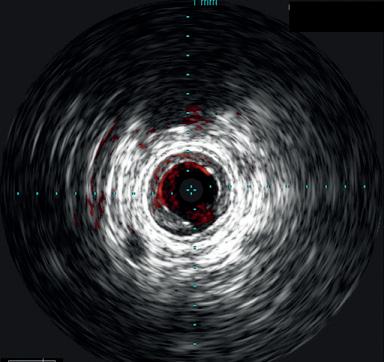

the Stellarex drug-coated balloon (DCB). Completion arteriogram showed marked improvement in flow but a possible dissection in the mid-segment of the SFA. IVUS’ unique ChromaFlo feature was then used to identify and confirm the areas of dissection (see figure 2) Most of the vessel had significant luminal gain but there were multiple areas of short-segment dissection. These were then treated with placement of a total of six Tack Endovascular System implants. The Tack implants were then post-dilated using plain old balloon angioplasty (POBA). Completion angiogram and IVUS (see figure 3) demonstrated resolution of the dissections. Follow-up ABI was 0.95 at rest.